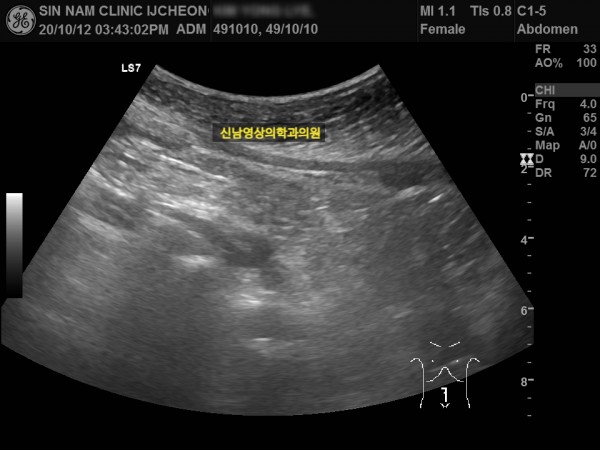

본 환자분께서는 사흘 정도 지속되는 복통과 고열로 내원하신 60대 중반의 환자분입니다.

복통 부위의 병변을 확인하기 위해서 복부 촬영과 복부 초음파검사를 진행했고, 맹장은 이상이 없고, 대장 주위로 복강삼출액(물)이 둘러싸고 있으면서 상행대장부위의 부종이 심하게 발견되었습니다.

원내 피검사상 백혈구 수치가 높아 대학병원 응급실로 전원 조치하고 응급수술을 받으셨고...

1년 뒤 수술 부위에 탈장이 발생하셔서 탈장 수술을 받으셨던 분입니다.